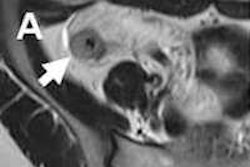

Increased mesenteric vascularity.

The problem was solved when researchers inadvertently tried a negative oral contrast medium.

"It became apparent that just filling the small bowel with negative contrast, food, or fluid was actually better than very bright contrast," Higgins said.

Decades of experience with barium imaging taught radiologists the value of complete bowel dissention for ensuring thorough examination. The use of neutral enteric contrast agents has proved to be especially well-suited for this role. Such agents allow water in the gut to remain there without bowel wall absorption, Higgins said.